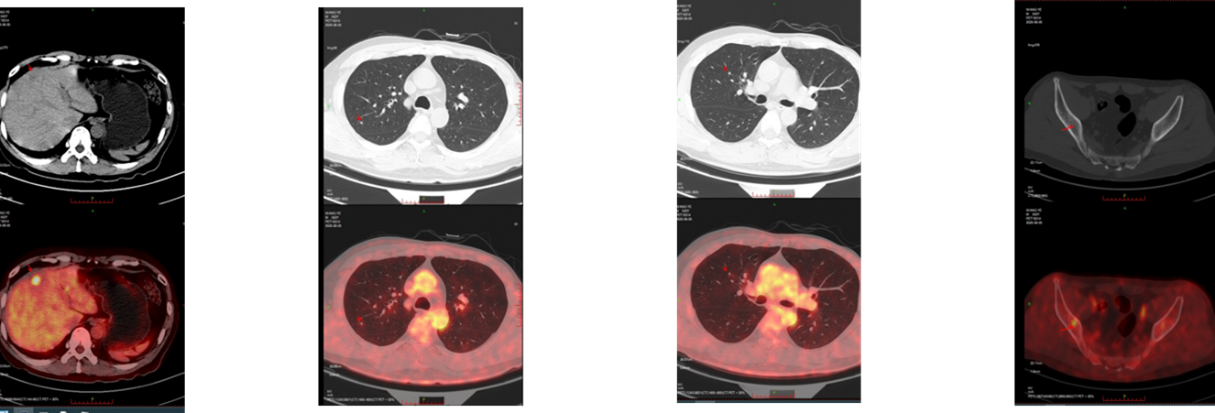

随后的PET/CT检查进一步证实了全身多发转移的情况,累及肝脏(S4低密度结节代谢增高)、双肺(多发实性小结节4-5mm)以及骨骼(右侧髂骨代谢轻度增高) 。

为明确病理性质及分子特征,指导后续精准治疗,临床团队对肝脏S4结节进行了超声引导下穿刺活检。2025年8月7日的病理报告证实为转移性乳腺癌。免疫组化显示ER维持强阳性表达(>90%),但PR表达下降至约5%,HER2仍为2+(FISH阴性),Ki-67热点区上升至30%,提示肿瘤增殖活性增强 。

患者的最终诊断为:1. 左侧乳腺浸润性导管癌改良根治术后复发(rT0N0M1, IV期),分子分型为Luminal B型;2. 继发性恶性肿瘤:肝脏转移、多发肺转移、骨转移;3. 基因变异状态:PIK3CA 突变阳性 。

针对这位男性、高危、PIK3CA突变的晚期患者,临床团队制定了强化的“四药联合”一线治疗策略,于2025年8月12日正式启动治疗,方案为:戈舍瑞林(去势)+ 依西美坦(AI)+ 达尔西利(CDK4/6抑制剂)+ 伊那利塞(PI3Kα抑制剂) 。

本例患者在接受含伊那利塞的四药联合治疗后,呈现了与临床研究结果相一致的快速缓解特征:治疗1个月余时,超声检查即提示病灶回声增强、体积缩小 ;治疗3个月时,MRI进一步确认肝S4主病灶从基线的15mm缩小至8mm,且增强扫描未见明确强化,提示肿瘤活性受到抑制 。这种“快速起效、深度缓解”的临床表现提示,以伊那利塞为核心的联合方案是应对高肿瘤负荷及内脏转移患者的优选策略之一。